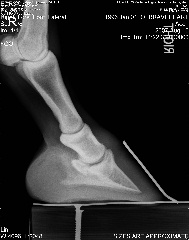

Posted on Friday, Aug 10, 2007 - 6:54 pm: We can trot on straight lines! Vet said he's at the limit from the coffin bone to the wall, that's not good, but he said he thought his angles looked ok. He thought that since the fetlock joints were off, he'd need more wall on the ;left front inside and more wall on the right front on the outside, then that should fix that. He said he'd like to see more sole, but he hooftested him and said his feet are rock hard so that should not be a worry for now. He's going to compare these to December's xrays and call. But based on what little he saw on the xrays and how he moved on the lunge, he said as long as I ride him in boots he should be just fine Here's a link to the xrays: https://s141.photobucket.com/albums/r59/wishes_album/xrays%20aug%2007/ Here are smaller versions: LF Lateral LF DP RF Lateral RF DP Edited to add that he was shocked that he could feel ribs when he asked Brave to move over But yes, he still is on a strict diet.

|

Posted on Friday, Aug 10, 2007 - 7:32 pm: Dr. O or anyone, Do his heels need to be lowered? I find it odd asking this question, but based on the xrays...Thanks! |

Posted on Friday, Aug 10, 2007 - 8:10 pm: Well, you can see from the laterals, his heels don't need to be higher. Are they back to the widest point of the frog? Breakover still looks too far forward to me if it's indicated by the white contrast line, but perhaps that's an illusion? |

Posted on Friday, Aug 10, 2007 - 8:43 pm: I don't think so... but they ARE better than they've been, I think, I just took these:Left front: Right front: